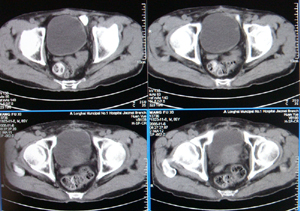

前列腺癌术后10余年,复查有无复发,请指教,图像做得不好,还望包涵

连续看还是前列腺的病变,考虑复发.

前列腺的病变,考虑复发.

结合病史,考虑前列腺癌术后复发。

前列腺增大,向上突入膀胱内,结合病史考虑前列腺癌复发可能。

图像太小,左侧膀胱壁似见不规则突起,前列腺突入膀胱,建议膀胱镜检查及前列腺增强检查。